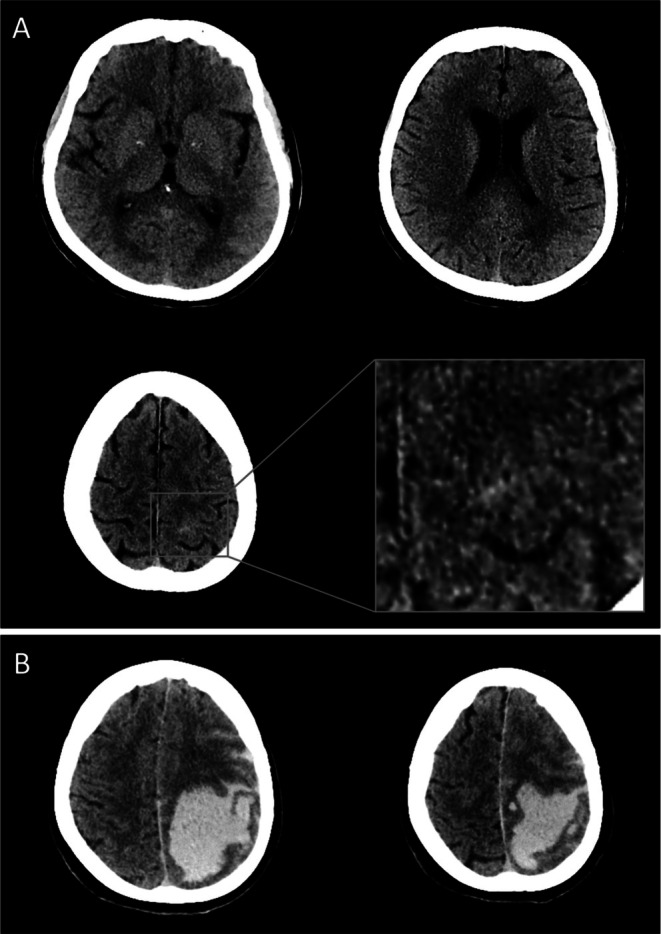

脑淀粉样血管病(CAA)已被认为是急性缺血性卒中(AIS)静脉溶栓(IVT)后发生大叶性脑出血(ICH)的风险之一。然而,在这种情况下,组织病理学CAA诊断的病例报告很少,只有一份报告暗示了CAA相关炎症(CAA- ri)的作用。我们报告一名65岁女性的临床、放射学和神经病理学观察,她表现为急性左半球症状,最初未显示颅骨计算机断层扫描(CT),并因疑似AIS接受了IVT。由于巨大的脑叶性脑出血和致命的结果,这一过程迅速复杂化。尸检显示严重的CAA,出乎意料地伴有跨壁CAA- ri,又名淀粉样蛋白β相关血管炎(ABRA),组织病理学证据为血管淀粉样蛋白β吞噬。重新评估初始影像学未发现CAA-RI的不对称融合性白质水肿征象,但怀疑为微小的左中央蛛网膜下腔出血,这是淀粉样蛋白的基底。载脂蛋白E (ApoE)基因型(ApoE)为ε3/ε3。作为第二例已发表的与ABRA相关的血栓溶栓死亡病例,以及少数确定为CAA的病例,本病例证实了CAA/CAA- ri是ivt相关ICHs的潜在潜在风险,敦促人们在AIS环境中认识到CAA相关的病理和临床放射学提示。这些发现暗示了血管Aβ吞噬与发病机制的相关性,证实了CAA- ri可能在没有明显水肿的情况下出现,强调了CAA/CAA- ri相关的局灶性神经功能缺陷(包括淀粉样蛋白发作)可能是IVT时间窗内潜在的AIS模拟,并敦促对IVT前CT扫描进行严格分析,即使是细微的脑区高密度,也可能提示老年患者的cah /淀粉样蛋白发作,促使考虑磁共振成像。

Cerebral amyloid angiopathy (CAA) has been implicated as a risk for developing lobar intracerebral hemorrhage (ICH) after intravenous thrombolysis (IVT) applied for acute ischemic stroke (AIS). However, there is a paucity of cases reported with histopathological CAA diagnosis in this setting, with a single report to imply the role of CAA-related inflammation (CAA-RI). We report clinical, radiological, and neuropathological observations of a 65-year-old woman who presented with acute left-hemispheric symptoms with an initially unrevealing cranial computed tomography (CT) and received IVT for presumed AIS. The course was rapidly complicated by a huge lobar ICH and a fatal outcome. The autopsy revealed severe CAA, unexpectedly with transmural CAA-RI, a.k.a. amyloid-β-related angiitis (ABRA), and histopathological evidence for vascular amyloid-β phagocytosis. Re-evaluation of initial imaging did not reveal signs of asymmetric confluent white matter edema characteristic of CAA-RI, but raised the suspicion of a tiny left central convexity subarachnoid hemorrhage, a substrate of amyloid spells. The genotype of the apolipoprotein E (ApoE) gene (ApoE) was ε3/ε3. Being the second published thrombolysis-associated fatality with ABRA and among the few with definite CAA, the present case confirms CAA/CAA-RI to be a potential hidden risk for IVT-associated ICHs, urging for awareness of CAA-associated pathologies and clinical-radiological hints in an AIS setting. The findings implicate the relevance of vascular Aβ phagocytosis in the pathogenesis, confirm that CAA-RI may present without prominent edema, highlight that CAA/CAA-RI-related focal neurological deficits (including amyloid spells) can be potential AIS mimics within the IVT time window, and urge for rigorous analysis of pre-IVT CT scans for even subtle sulcal hyperdensities suggesting cSAH/amyloid spell in elderly patients, prompting consideration of magnetic resonance imaging.